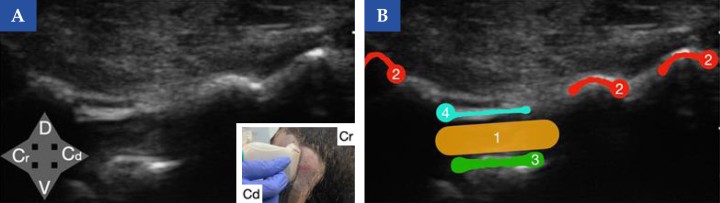

Referencias ecográficas del espacio lumbosacro en el perro (vista transversal). (A) Imagen ecográfica encorte transversal obtenida con sonda lineal a nivel del espacio lumbosacro en un perro. En la imagen inferior derecha se muestra la posición de la sonda ecográfica en el animal (Cr, craneal y Cd, caudal). (B) Esquema de identificación de las principales referencias anatómicas: crestas ilíacas (2), suelo del canal vertebral (3) y ligamento amarillo (4). El sitio de inyección se localiza en el canal vertebral (1), guiado por estas estructuras de referencia. ¿Para qué usar estatécnica?: Cirugía del tercio posterior y abdomen principalmente. Tratamiento de dolor crónico lumbosacro